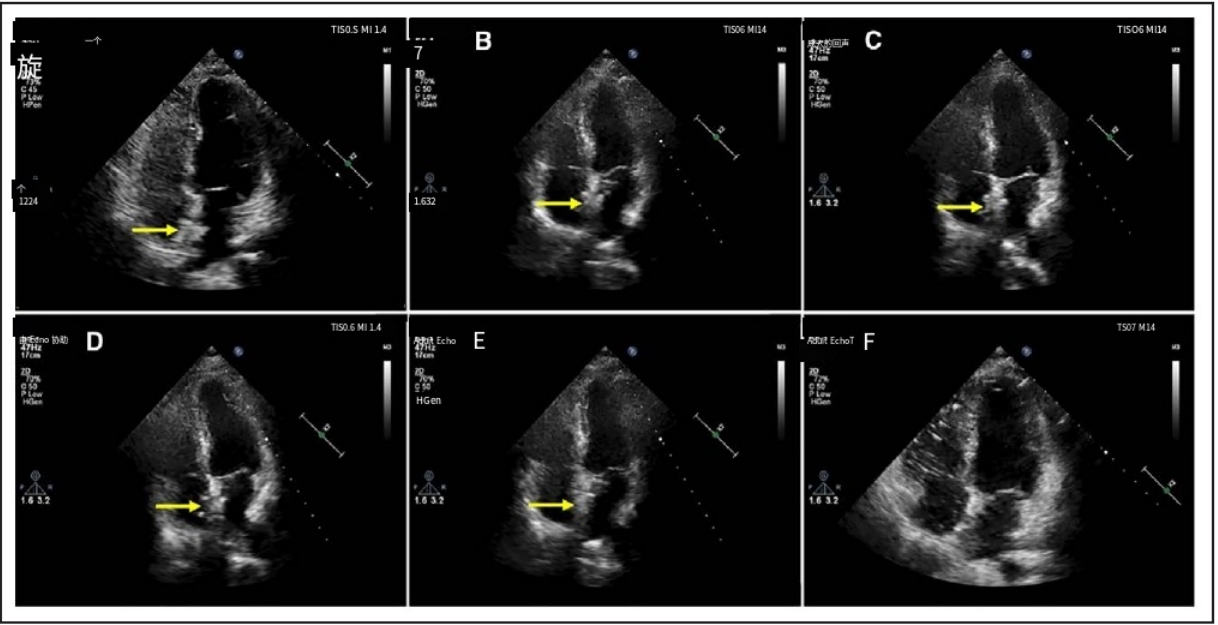

植入6个月后,超声心动图显示新型可降解卵圆孔未闭封堵器表现为自周围心内膜突出的高回声区。至24个月随访时,该封堵器与周围心内膜处于同一水平(图4;视频S3)。在1、3、6、12和24个月随访时,左盘在经胸超声心动图测量的高回声区降解比例分别为92.59%、83.41%、64.62%、16.41%和0%,而右盘分别为92.43%、83.44%、66.26%、17.37%和0%。在每个随访时间点,左、右盘突出的高回声区的降解比例具有可比性,两侧之间未观察到统计学显著差异。至植入后24个月,所有患者经胸超声心动图(TTE)下均未再观察到代表新型可降解封堵器的高回声区,提示封堵器已完全降解(视频S3点此详阅》》》》)。

图4. TTE下生物可降解封堵器在术后24个月随访期间的形态学特征变化

黄色箭头所示为生物可降解封堵器。出院前(A)、术后1个月(B)、3个月(C)、6个月(D)、12个月(E)及24个月(F)随访时均进行了经胸超声心动图四腔心切面检查。术后24个月时,封堵器已完全降解。